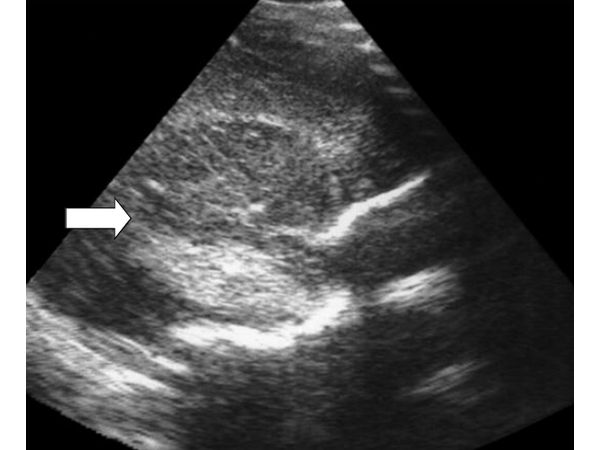

При проведении ультразвукового исследования головного мозга выявлено очаговое паренхиматозное образование в височной доле правого полушария с чёткими неровными контурами, повышенной эхогенности, однородное по эхоструктуре. Размеры образования 29х22х30 мм. При ЦДК кровоток в структуре не определялся. Учитывая клинические и лабораторные данные, а также неврологический статус, данное образование было дифференцировано как паренхиматозное кровоизлияние в височной доле правого полушария с незначительным смещением срединных структур в противоположную сторону.

При динамическом ультразвуковом исследовании размеры гематомы уменьшились до 21х17х25 мм. Эхоструктура кровоизлияния приобрела неоднородный характер с появлением мелких кист (1-2 мм) с более размытым контуром.